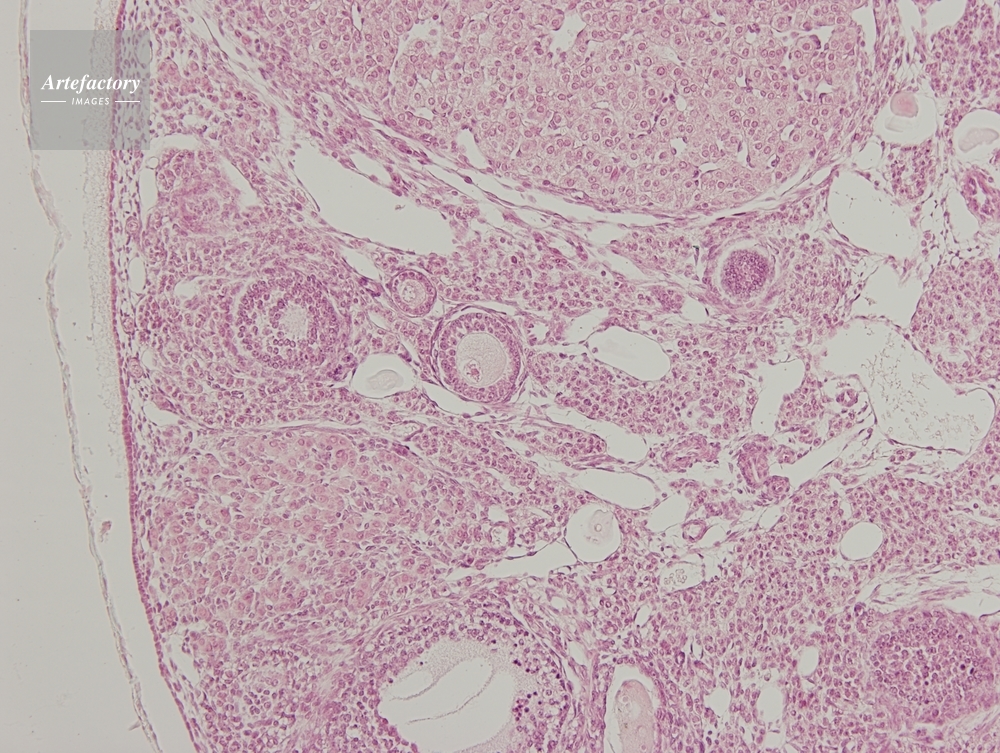

| 作品タイトル | マウス,卵巣 | モデルリリース | なし | |

| 作家 | OLYMPUS CORPORATION Technolab | プロパティリリース | なし | |